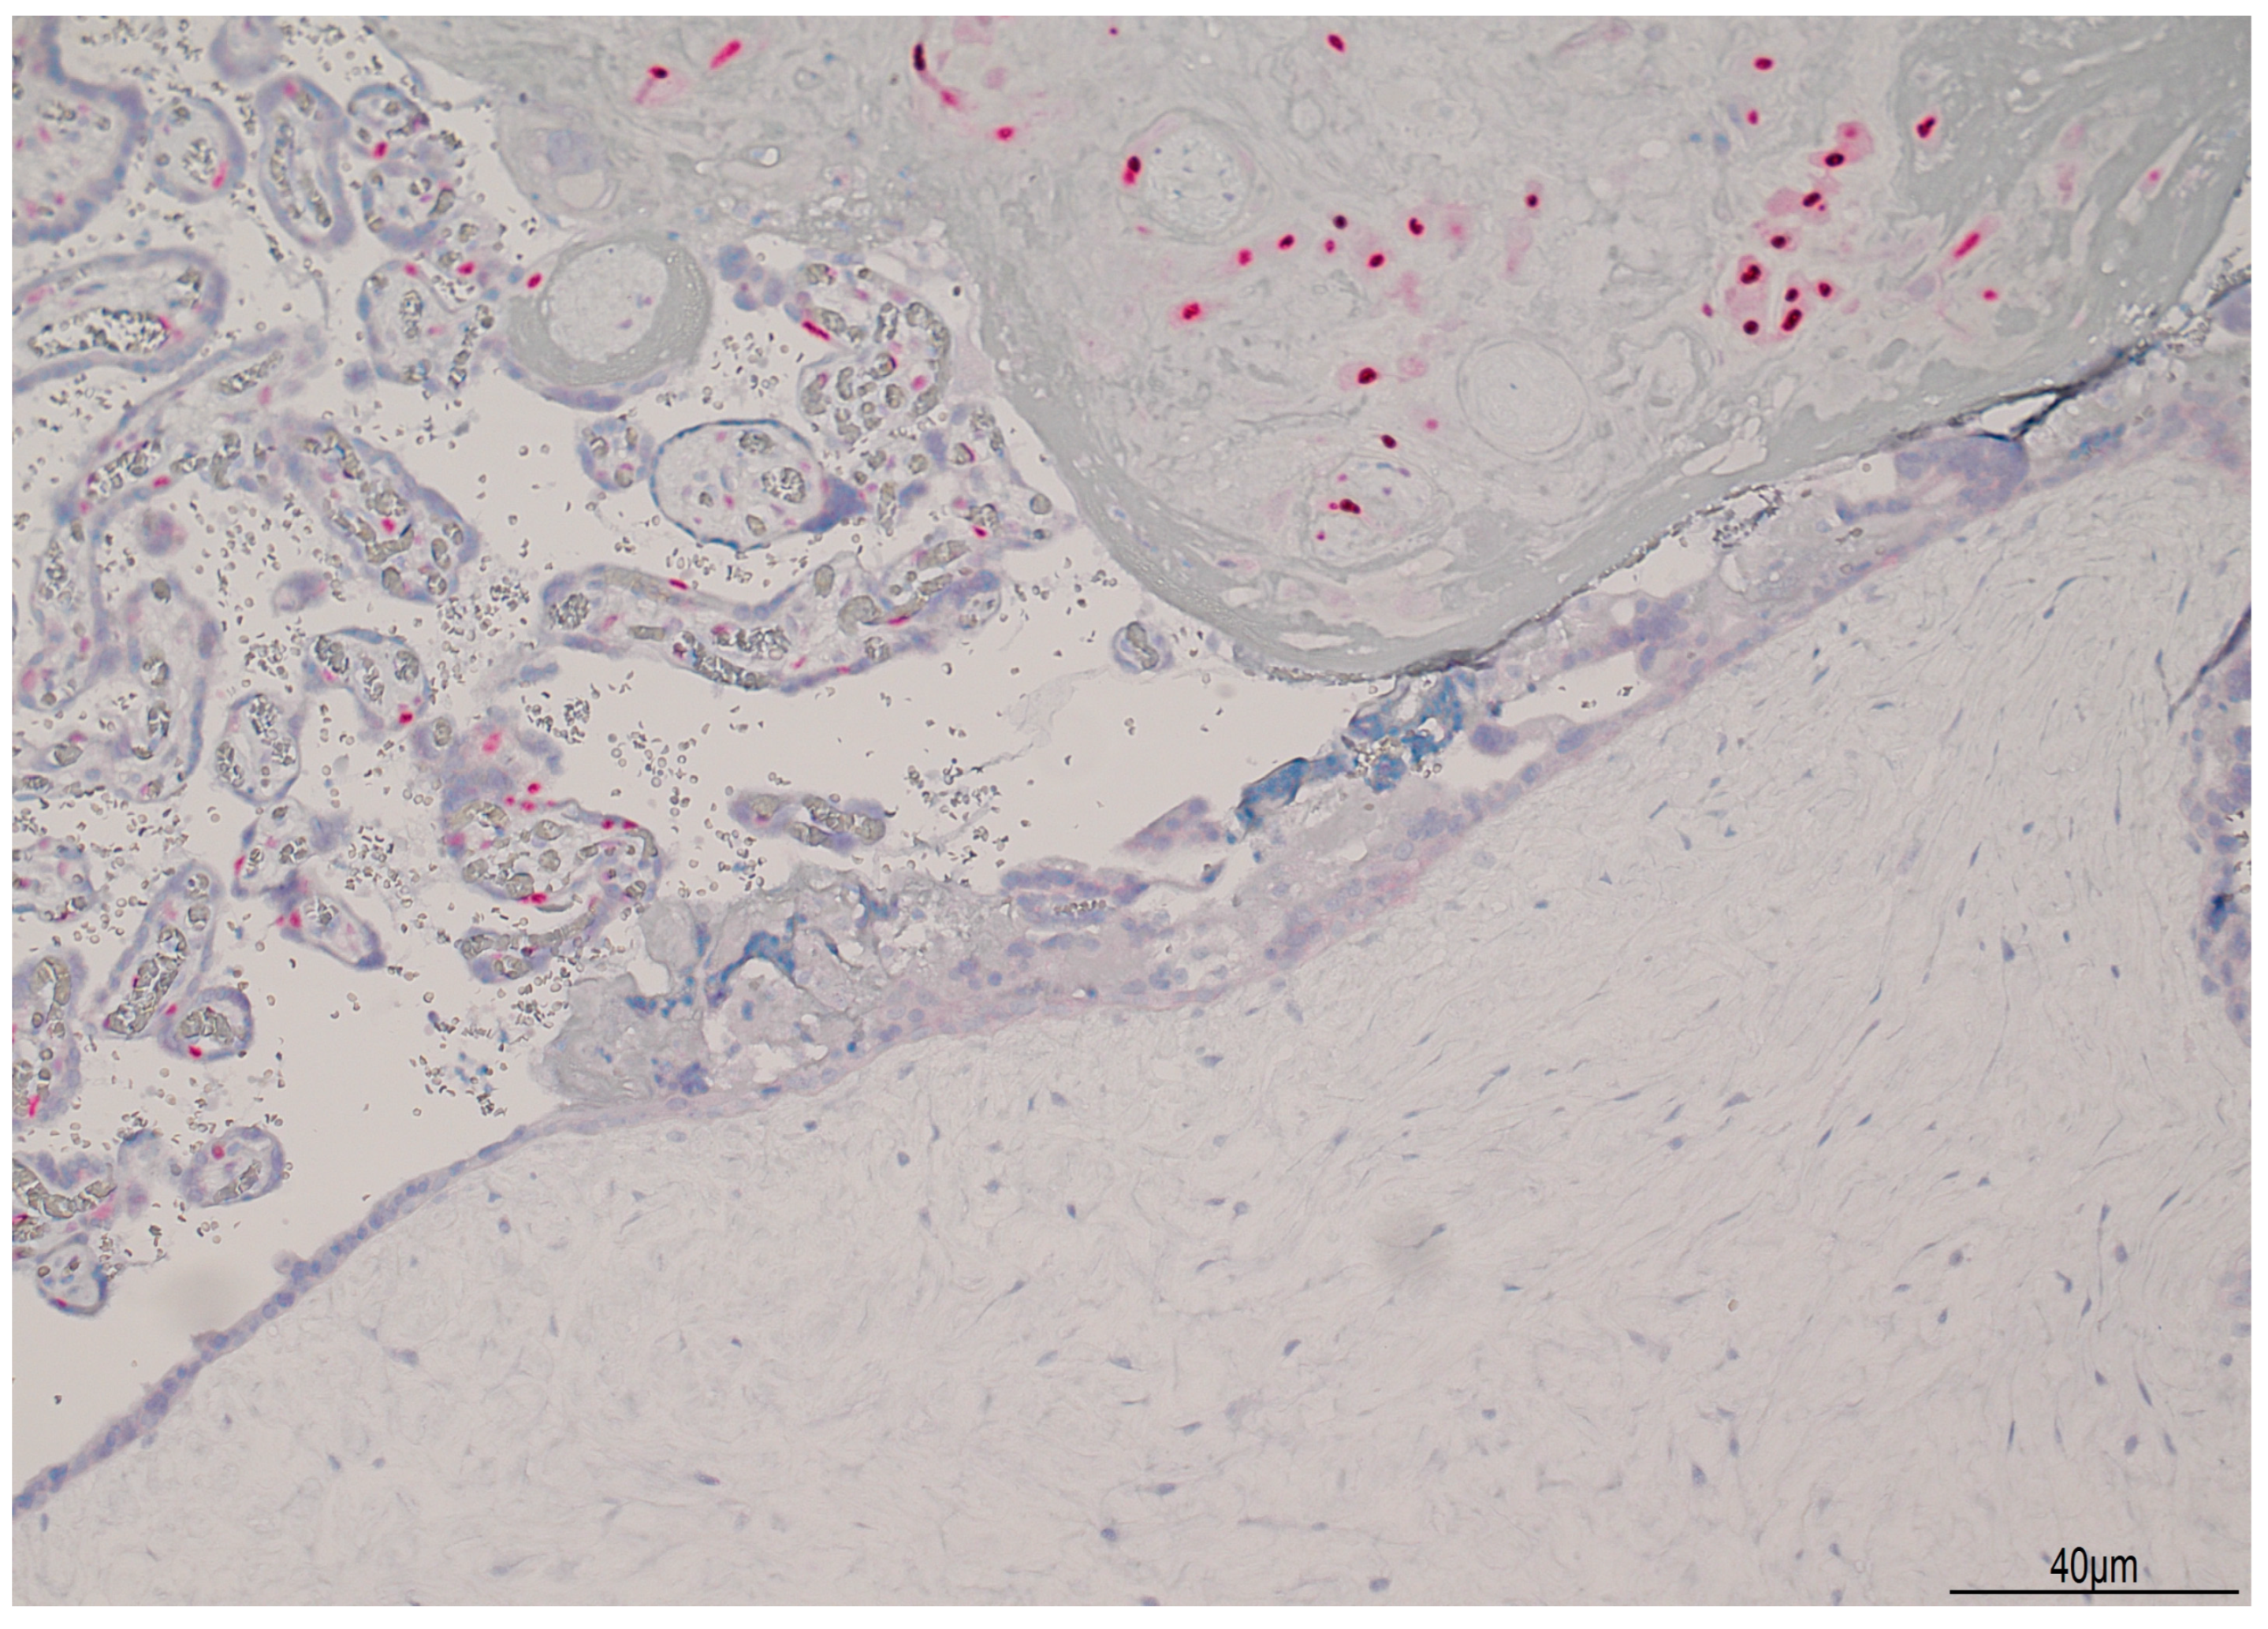

The referred US revealed an intrauterine pregnancy with a live fetus of normal size and morphology. US examination showed one placenta with a regular appearance, and adjacent to it, a cystic placental mass, measuring 70 × 50 mm (Figure 1).

Ultrasound images of hydatiform mole at 13 weeks of gestation: a normal intrauterine pregnancy ((A,B) left side) coexisted with a multicystic area ((A) star, (B) echographic cone), compatible with molar degeneration.

Considering the US finding of a second cystic placental mass in the absence of fetal structures, the clinical picture of vaginal bleeding, and the biochemical profile showing elevated maternal beta-hCG levels, a presumptive diagnosis of CHMCF was made. Although the definitive histological diagnosis, which could only have been made through bioptic sampling, was not pursued, the US images were sufficient in providing thorough counseling to the couple regarding maternal risks associated with pregnancy progression or legal TOP. In particular, the couple was informed that, according to data from the literature, the risk of preeclampsia and IUGR associated with the specific clinical condition could have been as high as 25% [9,11].